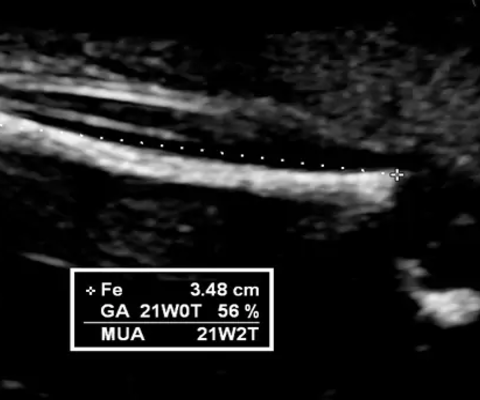

Như trên đã phân tích, từ tuần thứ 4 trái tim thai nhi đã có những nhịp đập nhẹ. Tuy nhiên để có thể xác định rõ ràng và chuẩn xác nhất thì các bác sĩ hoặc các cơ quan y tế thường khuyên các mẹ đi siêu âm vào tuần thứ 6 thậm trí là tuần 11, 14 để có thể lấy kết quả chính xác nhất.

Đối với thai nhi khỏe mạnh và phát triển bình thường thì nhịp tim sẽ dao động từ 120-160 lần/phút. Trong trường hợp trẻ di chuyển trong bụng mẹ thì khi siêu âm có thể lên đến 180 lần/phút. Theo sự phát triển của thai nhi, nhịp tim cũng sẽ dần đập nhanh hơn. Tuy nhiên trong trường hợp nhịp tim của trẻ lớn hớn 180 lần/phút thì đây có thể là dấu hiệu không tốt và cần được kiểm tra kĩ càng hơn.